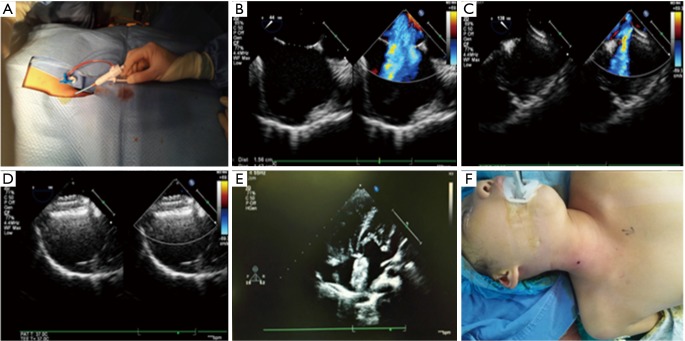

Figure 2.

(A) A 3-year-old patient of 12.5 kg with steerable introduce into the right jugular vein; (B) TEE showed that the diameter of ASD was 15 mm; (C) the tip of sheath perpendicular to the plane of ASD; (D,E) 18# occluder released with no residual shunt; (F) only a small puncture point left after the operation. TEE, transesophageal echocardiography; ASD, atrial septal defect.